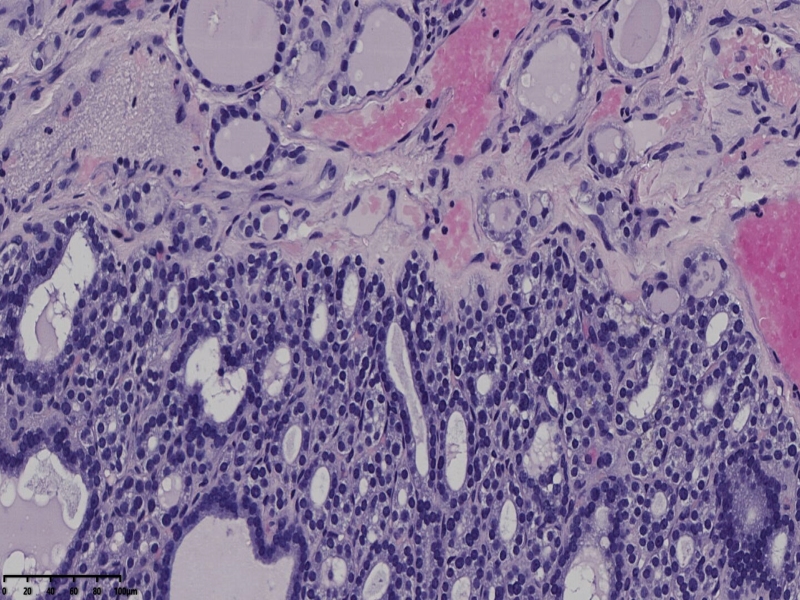

男、69、甲状腺左叶肿物,部分为囊性,囊内可见乳头状结构,上皮核重叠,没有核沟,没有毛玻璃样改变,没有核内假包涵体。255427

部分区域瘤组织与周围甲状腺组织分界明显,没有包膜样结构,滤泡结构为主,细胞异型明显。

会诊结果:(左叶甲状腺近峡部)甲状腺肿瘤,考虑为具有RAS核的乳头状癌,建议免疫组化及基因检测。